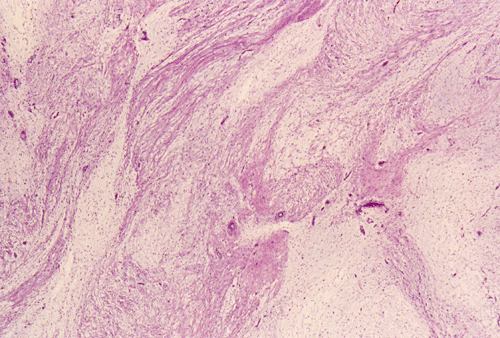

Panel A, B, and C are taken from the one area. Panel D, E, F, and G are taken from another area. Panel H and I are taken from areas with similar histologic features but distinctly separately on the same slide.

On low-magnifaction (Panel A and D), the lesional tissue appears to have generalized myomatous changes. No entrapped skeletal muscle fibers are found. The tumor cells tended to group into areas with variable cellularity that range from low- to, at most, moderate-cellularity. The hypocellular areas (Panel  B and C) contain sparsely spaced bland spindle cells in a bluish myxomatous background. The nuclei are elongated and mostly normochromatic. A few hyperchromatic nuclei are present and they are compatible with degenerative atypia (ancient change).

Islands with increased cellularity are present in some areas (Panel D, E, F, and G). These islands comprise about 30-40% of the lesional tissue. The cytologic features of the tumor cells in these areas are almost identical to that of the hypocellular areas except that the cellularity was increased. No mitotic figures are found in these areas. Focal hypervascularity are often found in areas with hypercellularity. No cellular condensation around blood vessels are noted (Panel  H and I).